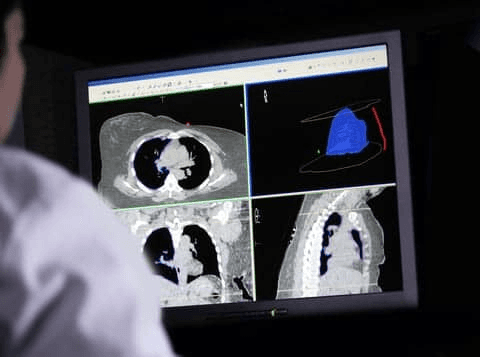

Live case-level signals on local AI performance to adjudicate outputs faster & more accurately